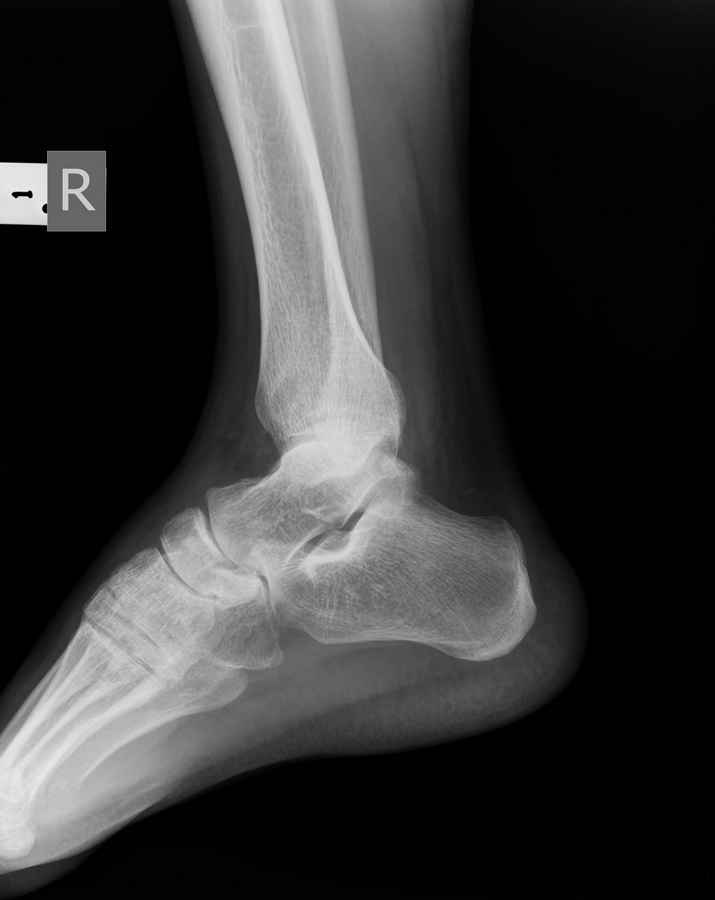

Мужчина 36 лет, пострадал около 8 месяцев назад в ДТП (водитель мотоцикла).

Подтаранный вывих лечили гипсовой лонгетой. Недиагностированным остался перелом ладьевидной кости, который беспокоит в настоящее время. Аваскулярный некроз кости, похоже.